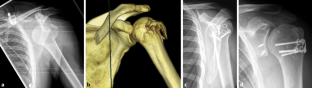

Ergebnisse

10 Patienten mit dislozierter Tuberculum-majus-Fraktur wurden mit der Bamberger Platte osteosynthetisch versorgt. Die Nachuntersuchung nach mindestens 6 Monaten zeigte einen Constant-Murley-Score von 94,2 Punkten (Spanne 91–98 Punkte). Das mittlere Alter betrug 45,6 Jahre (Spanne 29–68 Jahre).

Results

In all, 10 patients with displaced fractures of the greater tuberosity underwent osteosynthesis using the Bamberg plate. After a follow-up of at least 6 months, a Constant–Murley score of 94.2  points (range 91–98 points) was achieved. The patients’ average age was 45.6 years (range 29–68 years).

Abb. 15

Abb. 16

Abb. 17

Abb. 18